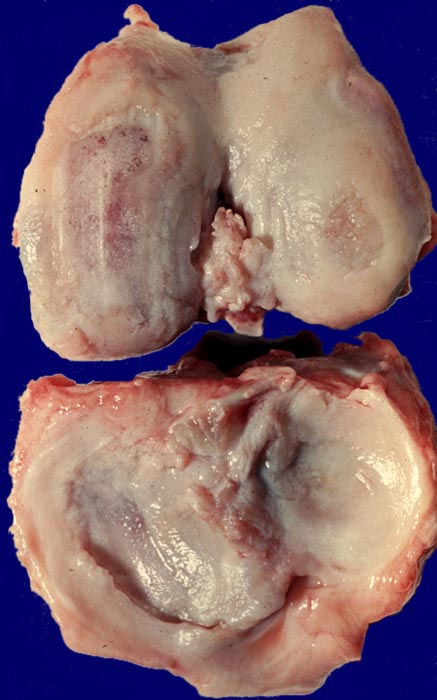

Der progrediente Knorpelverlust führt zum Freiliegen der knöchernen Deckplatte. Der subchondrale Knochen antwortet mit einer elfenbeinartigen Sklerose in Arealen vermehrter Belastung (=Eburnisation). Der traumatisierte subchondrale Knochen kann als Folge einer Knochennekrose pseudozystisch degenerieren (Geröllzystenbildung). Am Rand des Knochens, ausserhalb der Belastungszonen bilden sich irreguläre Knochenneubildungen (Randosteophytenbildung ev. mit Verdoppelung des Gelenkknorpels). Fragmentierungen dieser Osteophyten oder des Gelenkknorpels führen zu intraartikulären freien Körpern (=Gelenkmäuse) und einer Detritussynovialitis (> 1146) (> 1038) (> 539).

• Deformierte Gelenkfläche.

• Weitgehendes Fehlen des hyalinen Gelenkknorpels.

• Sekundäre Sklerose der freiliegenden Spongiosa mit Anbau von breiten Faser- und Lamellenknochensäumen an die alten Bälkchen.

• Leichte Osteoporose in der craniolateralen Entlastungszone.

• Herde von metaplastischem Faserknorpel in der Gelenkfläche.

• Randosteophyt, welcher über Resten des dort noch vorhandenen Gelenkknorpels entstanden ist (Verdoppelung des Knorpels).

• Nekrosebezirk in der Spongiosa (Geröllzyste) umgeben von einem Granulationsgewebssaum und Narbengewebe.